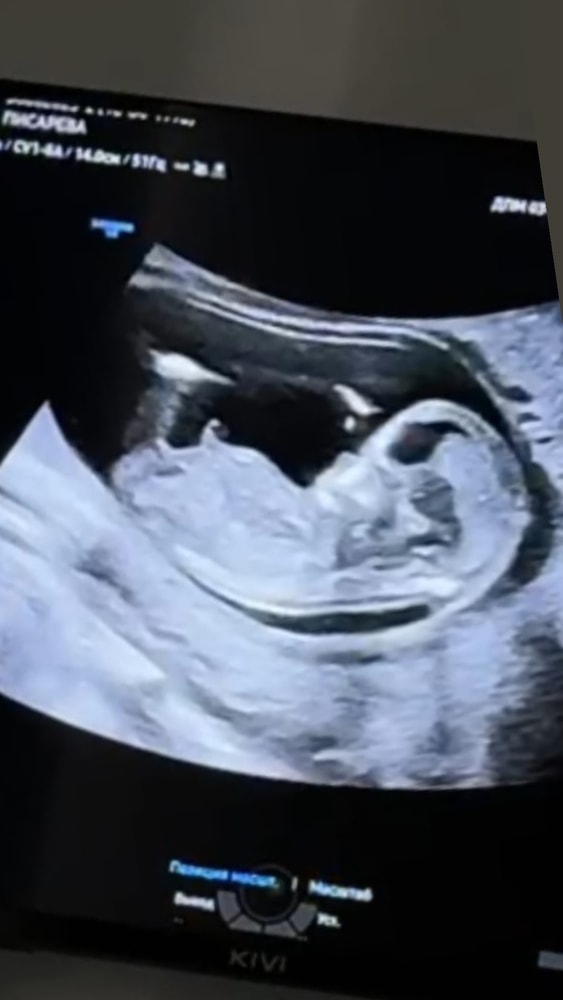

1 скрининг 12+3 , как думаете кто?

Пол малыша

Анастасия, я уже запуталась 😂 теперь не у себя не понимаю не у нее . Нам обоим кажется что у обоих мальчики

Tatiana Pisareva, вот обвела половой бугорок. Он параллелен. Но, так как я не профессионал) так что это всего лишь мое предположение, что девочка

Tatiana Pisareva, вот тут больше на мальчика. Но опять же не могу сказать что прям уверена на 💯

Анастасия, вот что интересно, что узист тоже туда сюда металась, потом сказала , что не скажет сейчас🤣

Tatiana Pisareva, что выше - это от ноги (часть бедренной кости зацепило).

Tatiana Pisareva, а вот на вашем фото, что в дневнике вашем - там на пацана похоже.